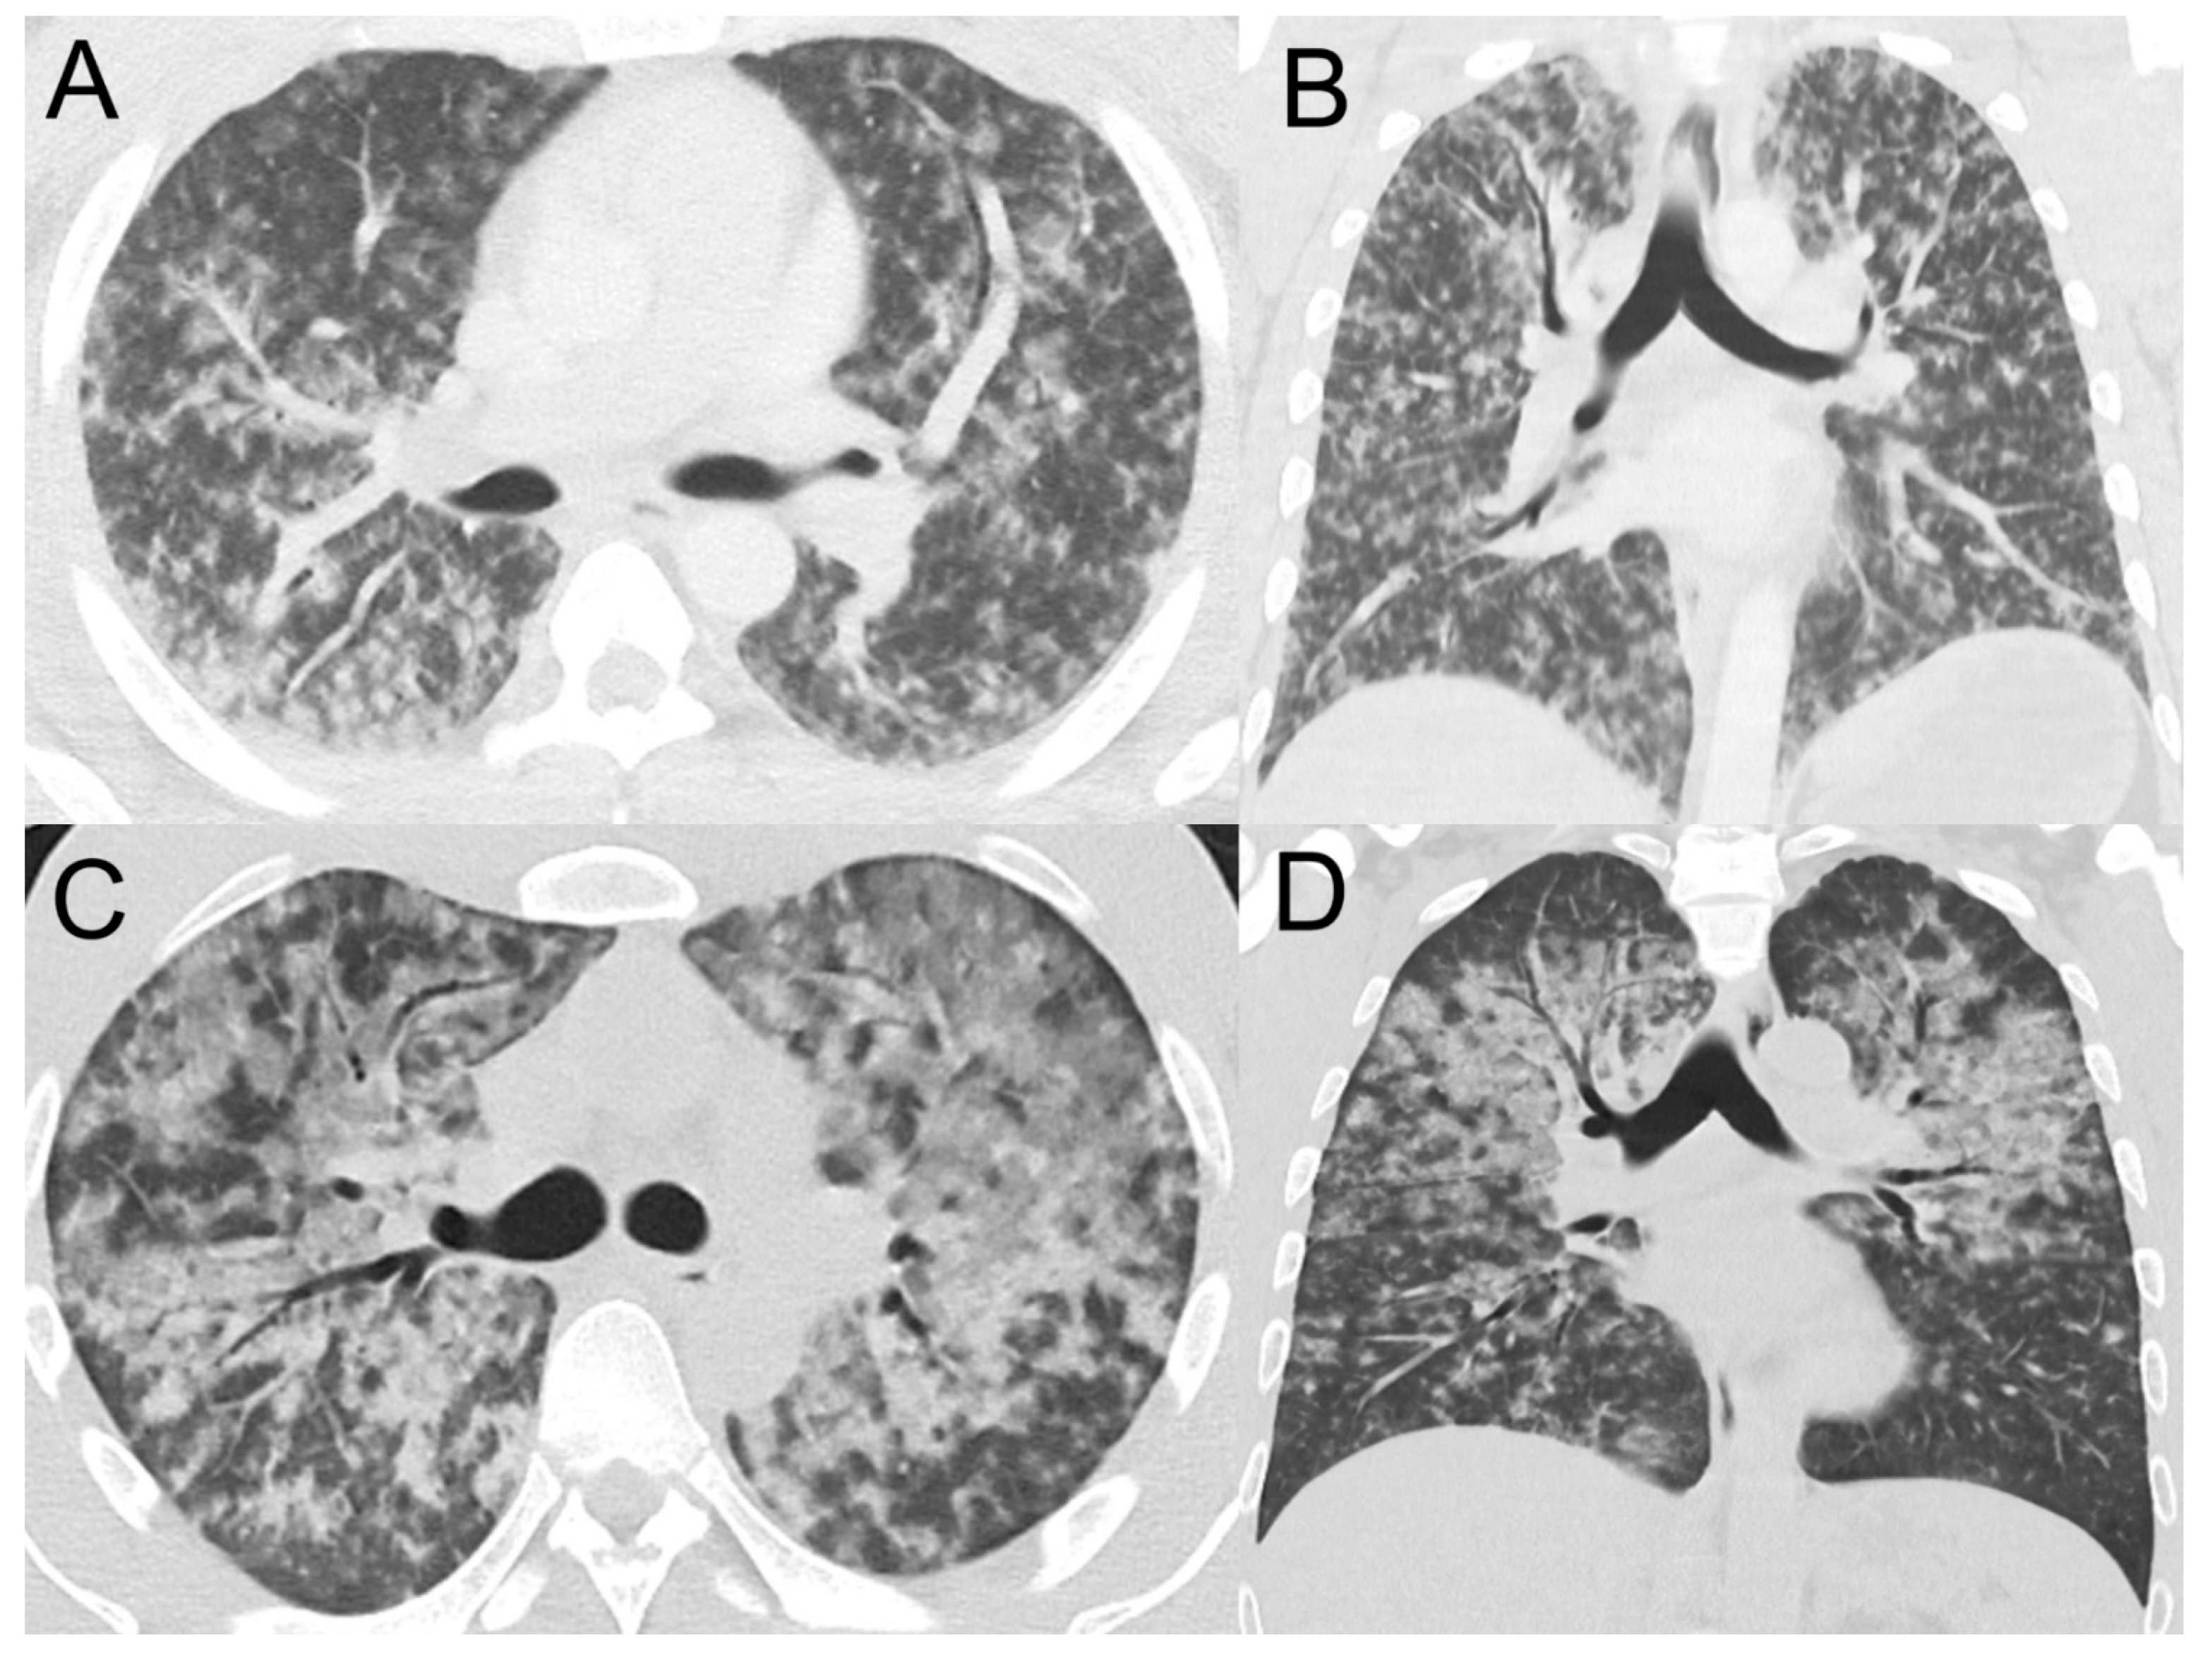

3.2. Pulmonary Haemorrhage

- Marchiori, E.; Lourenço, S.; Setúbal, S.; Zanetti, G.; Gasparetto, T.D.; Hochhegger, B. Clinical and imaging manifestations of hemorrhagic pulmonary leptospirosis: A state-of-the-art review. Lung 2011, 189, 1–9. [Google Scholar] [CrossRef]